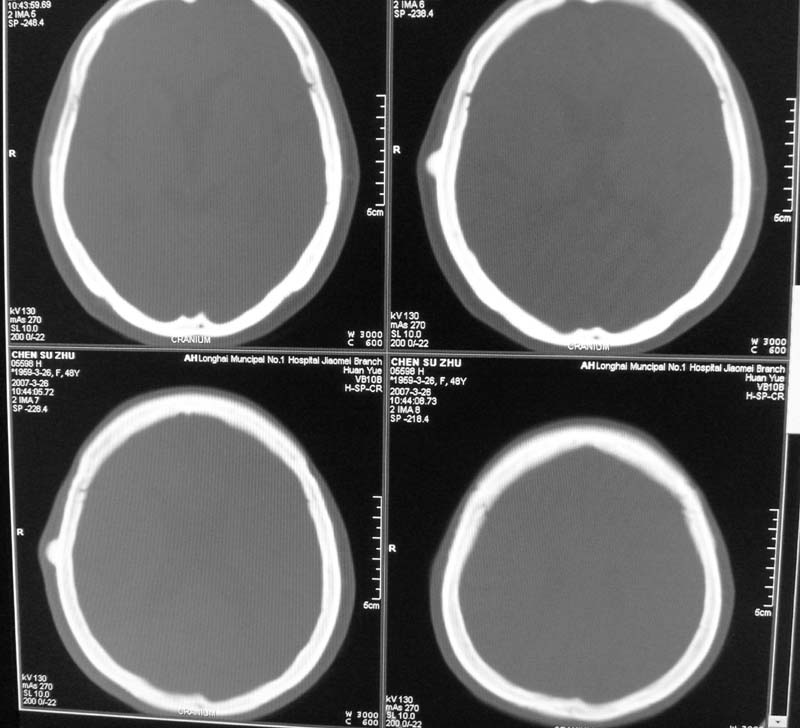

标题: CT8208:女,48岁,反复头晕半年余,无听力、视力障碍 [打印本页]

标题: CT8208:女,48岁,反复头晕半年余,无听力、视力障碍

患者,女,48岁,反复头晕半年余,无听力、视力障碍。病人已手术,结果明天传。

左侧桥小脑角区高密度肿块,周围无水肿及明显占位效应,岩骨尖受压吸收,内听道未见扩大,无听力异常,右侧颅骨外板高密度影,边缘锐利,考虑:左侧脑膜瘤,右侧颅骨骨瘤。左侧岩骨尖有破坏,三叉神经瘤待排。